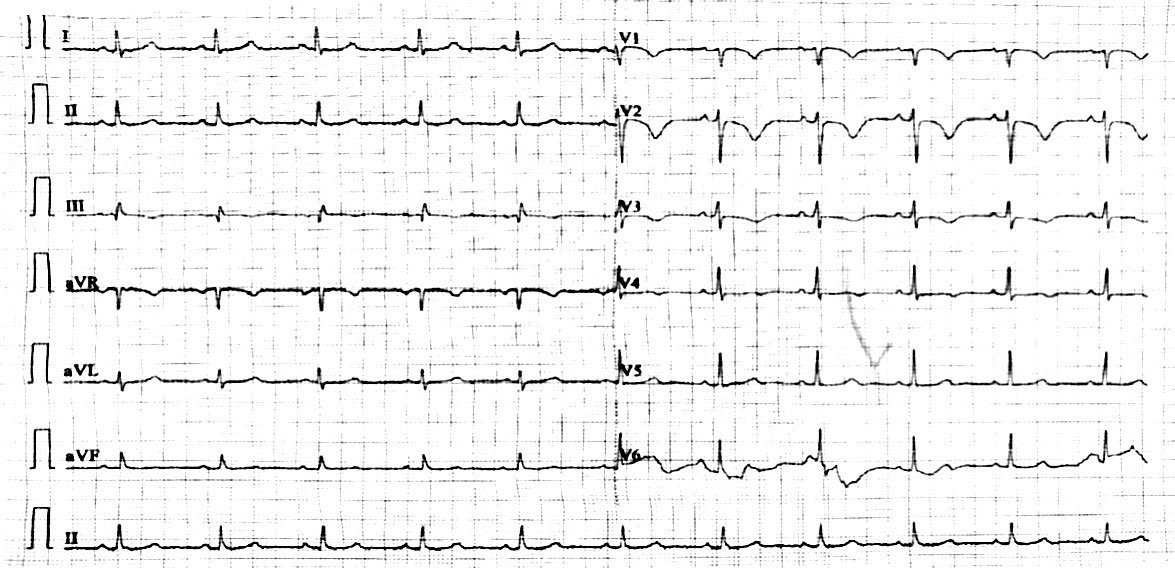

患者有5年高血压病史,3年前曾行子宫肌瘤切除术。已婚,孕2产1,已绝经。无特殊药物、外伤或疫区居住史,无吸烟饮酒习惯。入院查体:呼吸频率23次/min,血压111/73 mmHg,胸骨左缘第4肋间闻及2/6级收缩期吹风样杂音。实验室检查:D-Dimer 429 ng/mL(参考值0~243 ng/mL),B型利钠肽296 pg/mL(参考值0~100 pg/mL)。心电图提示窦性心律,SIQⅢTⅢ,V1-V4导联T波倒置(图 1)。超声心动图显示肺动脉及右心系统内多发囊性占位,右心轻度增大。入院后复查CTPA显示两肺段及段以上肺动脉多发充盈缺损(图 2)。入院诊断:肺动脉血栓栓塞症(中高危),右心系统占位(待查)。

| 图 1 入院心电图:窦性心律,SIQⅢTⅢ,V1-V4导联T波倒置 |

2 讨论 2.1 肺动脉内血栓负荷与D-Dimer水平不成比例成为重要的诊断疑点在本例中,患者最初表现为活动后胸闷和气短,容易被误诊为心脏或肺部疾病。心电图SIQⅢTⅢ征象、D-Dimer异常升高、心肌损伤标志物升高,CTPA显示两肺段及以上肺动脉多发充盈缺损,超声心动图提示右心系统占位,均提示血栓负荷较大[1-2]。初步诊断PTE似乎无异议,且抗凝治疗后D-Dimer水平呈下降趋势,但症状无明显改善。上述一系列问题突出了血栓负荷与D-Dimer水平不成比例时需要重新考虑诊断。经过多次凝血与纤溶相关的检验,排除了陈旧性血栓及纤溶功能异常等可能。结合患者双下肢动静脉彩超未见明显血栓证据,且无明确的诱发因素如无长时间久坐或长途旅行史,患者尚不具备常见的静脉血栓栓塞症的危险因素。需要补充的是,本例D-Dimer经过治疗有所缓解,不除外有血栓参与其中。